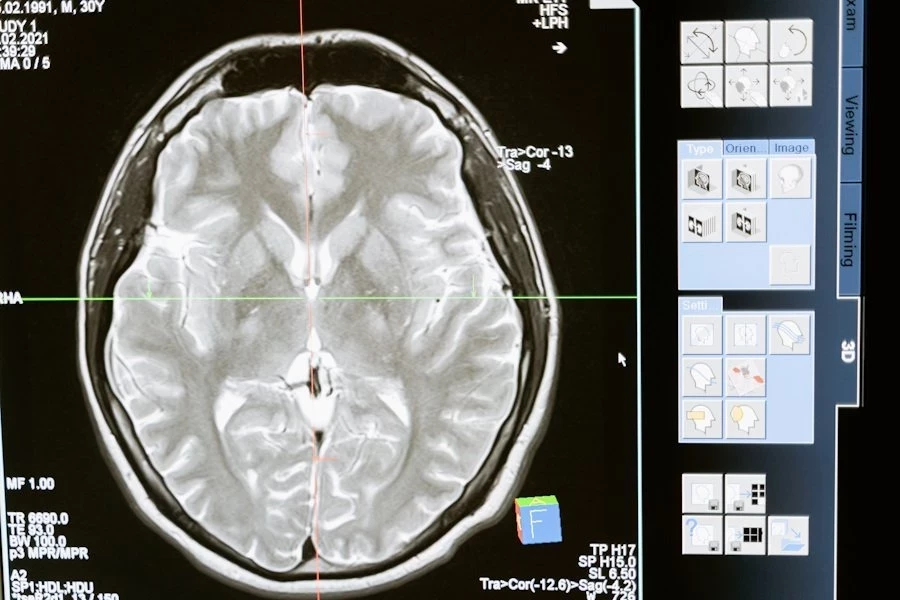

63-летняя Бет Роджерс из американского города Хейзен стала первым человеком в США, прошедшим экспериментальное лечение опухоли мозга с использованием вируса простуды. Уникальную операцию провели нейрохирурги Университета медицинских наук Арканзаса (UAMS), внедрив в опухоль аденовирус, который должен уничтожить раковые клетки, не затрагивая здоровые ткани, сообщает сайт университета.

Во время операции нейрохирург JD Day использовал специально разработанную канюлю, чтобы ввести аденовирус непосредственно в опухоль. Попав внутрь, вирус начал активно размножаться, атакуя злокачественные клетки. В отличие от традиционной химиотерапии, этот метод не требует повторных инъекций – вирус сам поддерживает атаку, пока в организме остаются раковые клетки.

Если эксперимент окажется успешным, этот метод может стать важным прорывом в лечении глиобластомы – одного из самых агрессивных видов рака мозга. Сейчас во второй фазе исследования CAPTIVE участвуют несколько медицинских центров США, но именно UAMS первым провел эту процедуру.